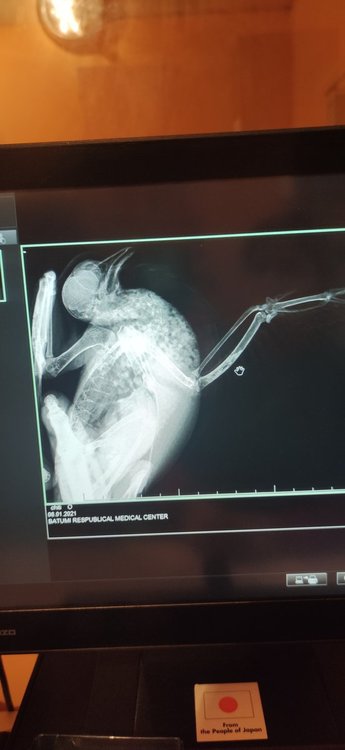

ksjsha Опубликовано 6 января, 2021 Автор #41 Опубликовано 6 января, 2021 (изменено) 42 минуты назад, ksjsha сказал: Ураааа,я такая реально счастливая?я договорилась за рентген в поликлинике,в ветклинике рентгена нету ? сейчас бегу за Гулей.Скажите,как именно мне его нужно делать и как Гулю дожить!? Я не уверена,что они знают?они же по людям. Вот так ,как на фото? Всех с рождеством! Я все сделала?не знаю радоваться или огорчаться?они говорят,что перелома нет. Я вот думаю,может я неправильно ее положила. Может плохо видно все ее косточки и суставы!? Что тогда с ней!?Ушиб что ли? Вот я высылаю вам снимки рентгена,что вы скажете!?Я ее положила на рентген, как на картинке сверху Изменено 6 января, 2021 пользователем ksjsha

ksjsha Опубликовано 6 января, 2021 Автор #43 Опубликовано 6 января, 2021 2 минуты назад, Beregovushka сказал: @ksjsha Вот тут внизу страницы посмотрите, как ястреб разложен в двух проекциях - на спине и на боку. https://www.mybirds.ru/health/rentgen.php Настройка аппарата должна быть как на кисть детской руки. Спасибо,но я уже сделала?не дождалась ответа. Мне кажется,что в этой части у нее проблема ,эта часть у нее висит. Или там все хорошо? Я почему- то уверена,что у нее оно сломанно и я ее неправильно как-то положила,что на снимке не видно ?

OFA Опубликовано 6 января, 2021 #44 Опубликовано 6 января, 2021 @ksjsha нужно Зосю, нашего доктора, звать в тему. Может она что-то увидит, она опытный доктор. По такому снимку плечевая засвечена, перелома вроде не видно, а вот сустав в каком состоянии, не знаю

маленький принц Опубликовано 6 января, 2021 #45 Опубликовано 6 января, 2021 @ksjsha поскольку форум пережимает фото обрежьте пожалуйста фотографии в электронной форме снимков рентгена нету? 2 часа назад, ksjsha сказал: Мне кажется,что в этой части у нее проблема ,эта часть у нее висит. надо было сделать снимок положив птицу на спину ВНИМАНИЕ за три часа до рентгена НЕ кормить и НЕ поить чтобы при переворачивании на спину не могла захлебнуться содержимым зоба постарайтесь получить рентген в электронной форме